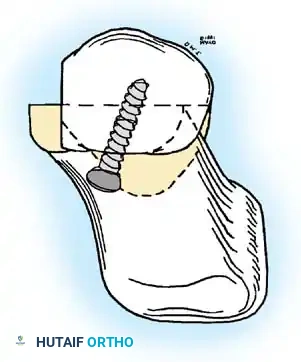

• Grasp the hallux in one hand and displace the proximal remnant medially so that, under direct vision, two longitudinal 0.062-inch Kirschner wires can be inserted.

• Hold the interphalangeal joint straight while drilling the wires from proximal to distal, emerging a few millimeters plantar to the nail plate.

• Return the foot to the corrected position, and drill the wires into the metatarsal head.

• While holding the metatarsal as far laterally as possible, cross the joint, and drive the wires out the plantar cortex just proximal to the head, while holding the hallux in 10 to 15 degrees of extension, neutral abduction, adduction, and rotation, and no translation dorsally or plantarward on the metatarsal head. The wires should penetrate only 2 to 3 mm past the cortex to avoid tenderness over the wires with weight bearing.

• If the Kirschner wires tend to “walk” on the rounded articular surface of the metatarsal head, use a small hemostat snugged up against the wire while it is being drilled to allow accurate placement. Proper placement of the wires and the desired position of the hallux on the metatarsal may require several attempts. The medial aspect of the proximal phalanx should not rest medial to the medial aspect of the metatarsal head.

• Place the hallux in the neutral medial-lateral plane and in 10 degrees of extension.

• Before the second wire is driven into the fi rst metatarsal head, place the hallux in proper rotation, using the plane of the nail as a guide. The initial length of the hallux is maintained by the wires. Later, collapse occurs when the wires are removed, but improved encapsulation of the hemiarthroplasty, by maintaining length for the fi rst few weeks, may help maintain a more desirable position long-term.

• Cut the wires off 2 to 3 mm distal to the skin edge.

• While standing next to the patient looking distally at the dorsum of the foot, dorsifl ex the ankle to neutral.

• Viewing the foot as the patient would, hold the fi rst metatarsal fi rmly, and move its distal end laterally. Hold this position with one hand, and use the other hand to place the hallux on the metatarsal head and out to length.

• While holding the fi rst ray straight with the foot vertical, have an assistant insert the wires from distal to proximal (Fig. 78-31G). Often these wires, which run through the fi rst metatarsal and hallux, hold the fi rst ray straight, and most of this correction is maintained after the wires have been removed.

• Close the capsule with a purse-string suture as previously described in the original technique (Fig. 78-31H to J).